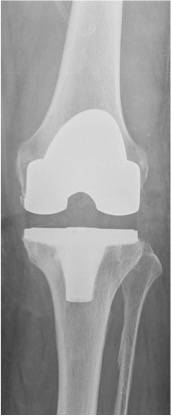

Das Röntgenbild zeigt eine Knieprothese.